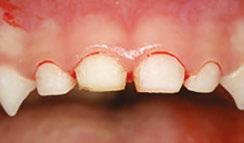

Over 10 years ago, we began Orthotropic® treatment for a 5 year, 3-month-old boy with a diagnosis of Pierre-Robin Sequence, Obstructive Sleep Apnea (OSA), and Failure to Thrive (Figure 1). With lack of forward development of the face com-

12 Pediatric Dental Practice US Volume 1 Number 1 PEDIATRIC PERSPECTIVE

monly seen in Pierre-Robin patients, his airway was compromised, resulting in OSA. The Failure to Thrive diagnosis likely resulted from insufficient growth hormone being released during the deeper stages of sleep. This treatment began before any permanent teeth erupted. Our goal was to eliminate OSA.

Orthotropics® uses removable appliances to laterally expand the upper arch while simultaneously advancing the upper anterior teeth to their proper place in the face. Then the mandible is developed forward. Orthotropics® is my preferred treatment in cases like this because it negates the head gear-effect producing better facial balance5 and also can result in substantial airway improvements (Figure 2).6

Figure 1: Pretreatment gallery Figure 3: Today, he’s a tennis player Figure 2: Pre- and posttreatment airways